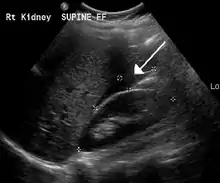

An ultrasound showing a gestational sac with fetal heart in the fallopian tube has a very high specificity of ectopic pregnancy. Transvaginal ultrasonography has a sensitivity of at least 90% for ectopic pregnancy.[4] The diagnostic ultrasonographic finding in ectopic pregnancy is an adnexal mass that moves separately from the ovary. In around 60% of cases, it is an inhomogeneous or a noncystic adnexal mass sometimes known as the "blob sign". It is generally spherical, but a more tubular appearance may be seen in case of hematosalpinx. This sign has been estimated to have a sensitivity of 84% and specificity of 99% in diagnosing ectopic pregnancy.[4] In the study estimating these values, the blob sign had a positive predictive value of 96% and a negative predictive value of 95%.[4] The visualization of an empty extrauterine gestational sac is sometimes known as the "bagel sign", and is present in around 20% of cases.[4] In another 20% of cases, there is visualization of a gestational sac containing a yolk sac or an embryo.[4] Ectopic pregnancies where there is visualization of cardiac activity are sometimes termed "viable ectopic".[4]

Ultrasound image showing an ectopic pregnancy where a gestational sac and fetus has been formed.